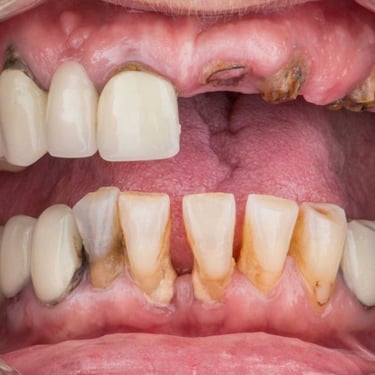

Edentulismo completo

El edentulismo completo es la ausencia total de dientes en una o ambas arcadas.

Los pacientes tienen dificultad para masticar, hablar y pueden sentirse incómodos con su apariencia.

El tratamiento puede incluir la colocación de una prótesis completa sobre implantes, proporcionando una solución fija y estable